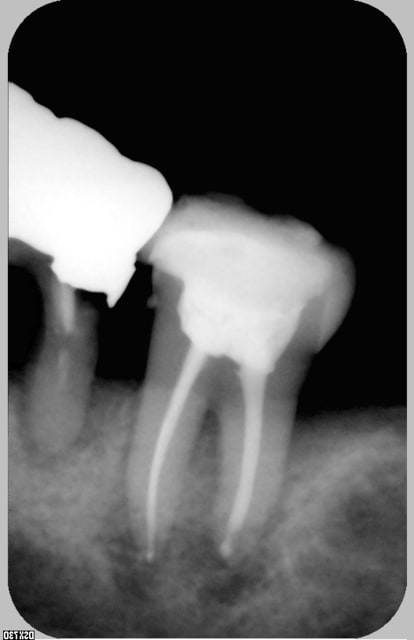

Je relance ce post pour avoir votre avis sur ce cas : jeune femme 25 ans en urgence douleur sourde d'apparition brutale sur 16 dévitalisée .Test morsure positif et papille mesiale enflammée , je démonte l'obturatio et voila ce que je mets en évidence ( il y a en plus un mv2 non obturé).Extraire d'emblée cette dent me fait mal au coeur : y aurait il un traitement à tenter ou que vous auriez réalisé avec succes ? ( la felure ne traverse pas entièrement la dent: localisée en mésiale )

Merci.